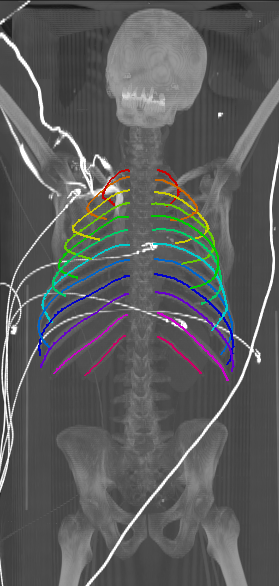

With an average Euclidean distance error of 0.787 mm, we obtained an overall result that is generally better compared to what is reported in the state of the art. Although, it needs to be kept in mind that results are unfortunately not directly comparable as both the data sets as well the evaluation metrics significantly differ across prior work. Similarly to the results obtained on the probability maps, distance errors are significantly higher for first and twelfth rib compared to the rest of the rib cage. As discussed, this is caused by the intrinsic challenges of these ribs, but certainly also an affect of error propagation in that sense that the quality of the probability maps also impacts centerline extraction. Interestingly, the right ribs are generally slightly worse compared to the left ribs, probably due to a slightly unbalanced data set with more challenges on the right side. Figure 5 shows the centerlines which were automatically generated using our walker algorithm from the corresponding network outputs displayed in Figure 4.

Refer to caption

Figure 5: Automatically generated centerline splines associated with the FCNN outputs displayed in Figure 4. The selected case above display common difficulties which are inherent in the data set, such as pads (a) or cables (b), internal devices such as pacemakers (c), stents (d), spinal (e) and femural/humeral implants (f), injected contrast agents (g), patient shape variations such as scoliosis (h), limited field of views (FOVs), i.e. partly missing first (i) or twelfth rib (j).